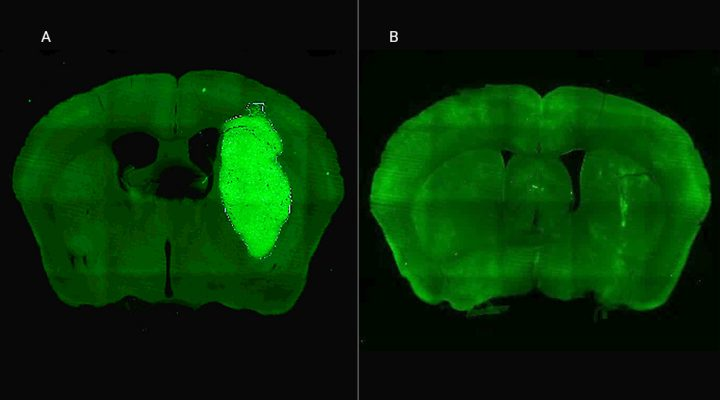

El tratamiento experimental se centra en el glioblastoma, el tumor cerebral primario maligno más común en adultos y altamente resistente a la quimioterapia y radioterapia. #Cancer #Salud #CONICET #Ciencia #Tecnología Lab Candolfi, FMed.⭐⭐⭐ periferia.com.ar/investigacion/…

El tratamiento experimental se centra en el glioblastoma, el tumor cerebral primario maligno más común en adultos y altamente resistente a la quimioterapia y radioterapia.

Descubren una estrategia experimental para frenar el glioblastoma, el tumor cerebral más agresivo 🔬🧠‼️ Charlamos con integrantes de Lab Candolfi, FMed.⭐⭐⭐ sobre este trabajo de ciencia básica en neurociencias que podría abrir la puerta a futuros tratamientos: acortar.link/A9Dgc7

Descubren una estrategia experimental para frenar el glioblastoma, el tumor cerebral más agresivo 🔬🧠‼️

Charlamos con integrantes de <a href="/CandolfiLab/">Lab Candolfi, FMed.⭐⭐⭐</a> sobre este trabajo de ciencia básica en neurociencias que podría abrir la puerta a futuros tratamientos: acortar.link/A9Dgc7

🧠Especialistas del CONICET logran frenar un tipo de cáncer cerebral en estudios preclínicos con una novedosa estrategia terapéutica.

🟣Especialistas del CONICET logran frenar un tipo de cáncer cerebral en estudios preclínicos con una novedosa estrategia terapéutica.⬇️ conicet.gov.ar/especialistas-…